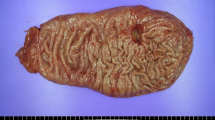

Xenograft tumor model, immunohistochemical staining, and EBV in situ hybridization

GC cells were injected subcutaneously into BALB/c nude mice. NCC24 cell lines were injected in both flanks of four mice and SNU-719 cell lines were injected in five mice. The tumor volume was measured periodically until tumor extraction. Tumor masses derived from xenografts were removed surgically and fixed with buffered formalin. Immunohistochemical staining with anti-MLH1 antibody and EBV in situ hybridization with silver staining were performed on glass slides as described previously [15]. Animal procedures were approved by the Biomedical Research Institute of Seoul National University Hospital (approval no.3520160085).

Tumorsphere formation assay and xenograft tumor model were developed to determine the effect of stemness in MLH1-negative GC cells. MLH1-negative SNU-719 and NCC24 cells showed a significant decrease in sphere number compared with control cell line (P < 0.001 and P < 0.001, respectively, for SNU-719, and P = 0.003 and P < 0.001, respectively, for NCC24) (Fig. 4a). However, AGS cell line did not show decreased number of tumor spheres when MLH1 expression was downregulated (Supplementary Fig. 1). In the xenograft tumor model, tumors with MLH1 deficiency were significantly decreased in tumor volume compared to those injected with control cell lines (P < 0.001 and P < 0.001 for SNU-719 and NCC24, respectively) (Fig. 4b). We confirmed that MLH1-negativity and EBV-positivity were not affected during the xenograft procedure (Fig. 4c). Cell surface proteins CD44 and CD133 were selected to determine stemness of cell lines, since they are considered as cancer stem cell makers in EBV-positive cancer or gastric cancer [19,20,21]. A decrease of surface stem cell marker CD44 expression, induced by MLH1 knockout, was observed significantly in NCC24 but was not as significant in SNU-719 cells (Fig. 4d). The surface protein expression of CD133 was not detected in both cell lines, which was also confirmed by immunohistochemistry of the xenograft tumor (Supplementary Fig. 2). Therefore, regardless of the MSI status, reduction in stemness was observed in MLH1-negative EBV-positive GC cell lines both in vitro and in vivo.

Tumor stemness, MLH1 expression, and maintenance of EBV-positivity in GC cell lines. a Tertiary tumorspheres (left) and its count in GC cell lines (right). b In xenograft tumor models, control cell lines were injected to the right flank and MLH1 knocked-out cell lines were injected to the left flank (left). Tumor size periodically measured before tumor extraction (right). c Tumor mass obtained from xenograft were immunostained with MLH1 (upper) or stained with silver for EBV in situ (lower). d Flow cytometry for CD44 expression in GC cell lines